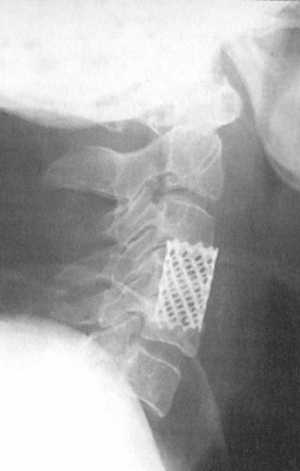

Рис. 4.1. |

пластиной. В последнее время мы все шире применяем титановую конструкцию состоящую

с полой титановой трубки перфорированной множеством отверстий. Титановая трубка

заполнялась аутокостью и устанавливалась при тракции головы между телами неповрежденных

позвонков (рис. 4.1). Если выполнялась корпорэктомия 2-3-4 позвонков титановую

трубку необходимо фиксировать пластиной по той же методике, которая описана